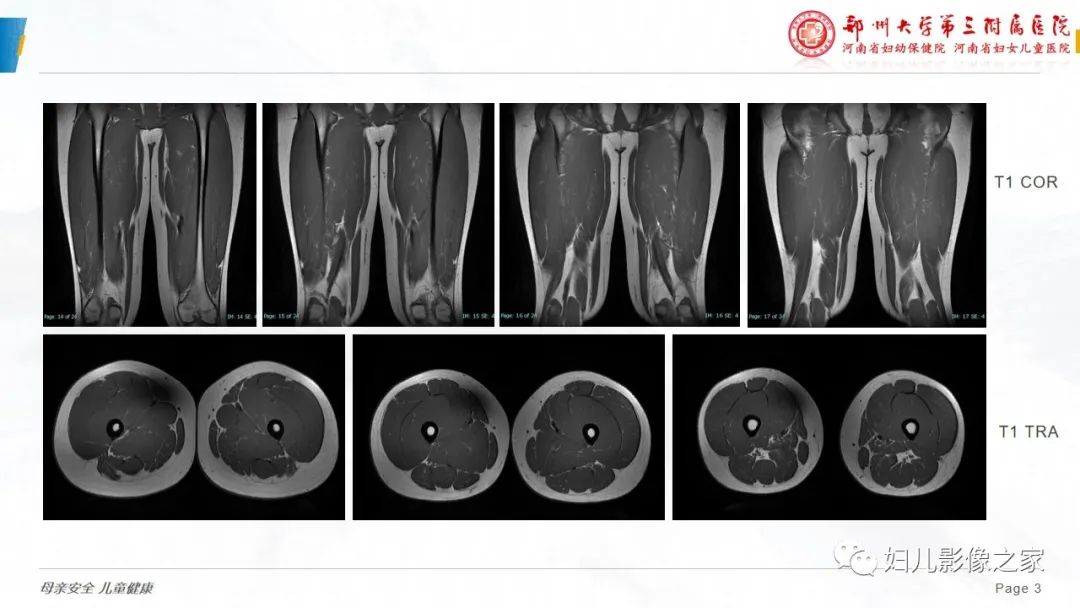

【病例】横纹肌溶解症1例MR影像-3